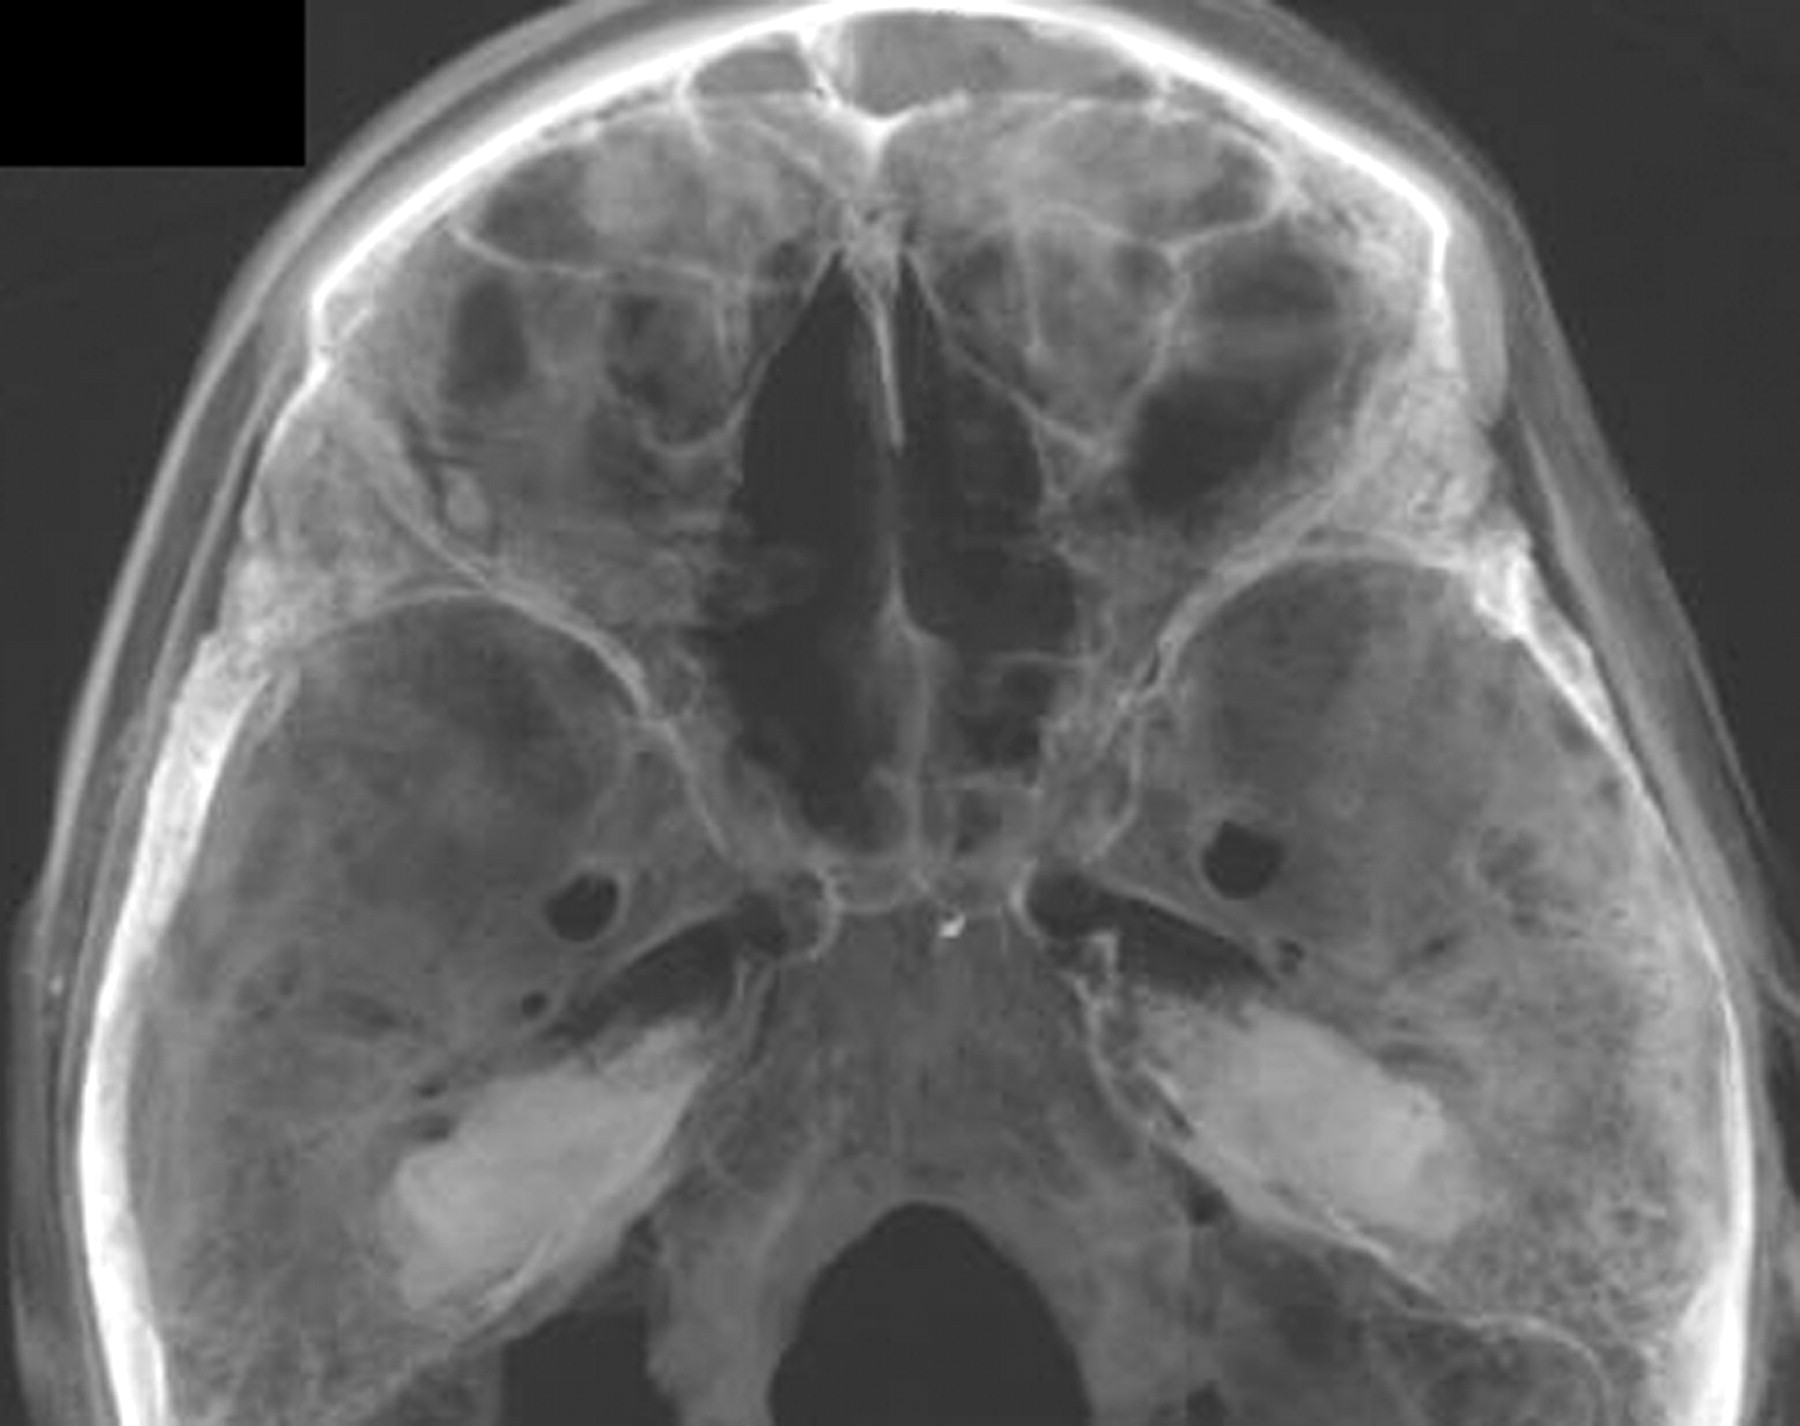

All of the features visible in MDCT were also visible in fpVCT. As expected, fpVCT offered higher spatial resolution and greater anatomic detail. Therefore, in the analysis that follows, only fpVCT images are shown and analyzed. The volumetric images showed excellent bony detail and the soft tissue, including the skin surface. A photograph of the mummy head is shown in Fig 1. The wrapping covering the skin surface can be visualized clearly in this photograph.

Calvaria

Figure 2 shows surface-rendered views of the skull of the mummy from different viewpoints. As can be seen, the calvaria are intact above the level of the orbital rims. The bone is well mineralized and the cortical thickness normal, indicating that Djehutynakht was probably young and did not suffer from osteoporosis or any other metabolic bone disorder.

Anterior Cranial Fossa.

Figures 4 and 5 depict the anterior and middle cranial fossae. In the anterior skull base, the middle portion of the cribriform plate has a large defect, just posterior to the crista galli. The ethmoid air cells in this section have been removed. This defect makes the anterior cranial fossa communicate with the nasal cavity and the outside. It also makes the cranial vault communicate with the oropharynx through the portion where the soft palate would have been and through the choanae. The hard palate is intact as are the medial and superior walls of the orbits.

Middle Cranial Fossa.

The sphenoid bone is intact (Figs 4 and 5). The sella turcica can be visualized and has not been violated. The hamuli of the lateral pterygoid plates are intact bilaterally. The major foramina of the skull base can be visualized.

Posterior Cranial Fossa.

At the base of the posterior cranial fossa, adjacent and to the left of foramen magnum, there is a large defect in the occipital bone (Fig 6). It occupies the space between the foramen magnum and the petrous ridge and is confluent with the jugular foramen. The adjacent styloid process has been fractured. In the desiccated mummy, this defect in the bone makes the posterior cranial fossa communicate with the posterior oropharynx; in a cadaver or in life, there would have been intervening soft tissue. The rim of the foramen magnum itself is intact.

Inferior views looking up (top and bottom left), and a superior view looking down (bottom right) showing the defect in the posterior cranial fossa, illustrated with the help of 2 clip planes. Note the jagged nature of the margins of this defect.

The margins of the defect are somewhat irregular, suggesting that the bone had been removed piecemeal, rather than having been sharply cut away as a single piece with a bone saw. The bone defect is well removed from the area of superficial tissue loss on the posterior surface of the skull, making it extremely unprobable that the latter provided access to the skull base. Access to this area would have been most expeditiously gained from a lateral retromastoid approach.

Nasal Structures and Palate

The nasal bones are intact. The external appearance of the nose has been restored by the linen (Fig 7). The nasal turbinates on the left have been removed, and, as noted earlier, there is a defect in the left side of the cribriform plate. The right side of the cribriform plate has a smaller defect. The nasal septum is partially resected, because the middle and superior part of the nasal septum is missing. The anterior nasal septum and the nasal philtrum are present. There is diastasis of the suture between the frontal process of the maxilla and the nasal bones bilaterally.

Facial Structures

The head was wrapped in 7 layers of a thin, gauzelike linen that is not very attenuating to x-rays, as measured by the CT number. The weave of this material is hard to discern, though it can be distinguished from skin by its lower attenuation. The thickness of the linen molding varies and was shaped to give form to the face, especially where bone has been removed (eg, bilateral zygomas, Fig 7). In parts of the head, air has dissected between the cloth and skin surface. No facial lacerations or deliberate incisions are identifiable because of the preparation.

Zygoma and Zygomatic Arch.

There is a displaced zygoma complex or tripod fracture on the left (Fig 8). There is no evidence of healing, and these fractures are postmortem. There is diastasis of the sutures between the zygoma and its neighboring bones (ie, the left maxillary bone, the frontal bone, and the greater wing of the sphenoid). The body of the left zygoma is dislocated into the space of the left maxillary sinus. The posterior part of the left zygoma and the entire right zygoma have been removed.

Missing right zygoma (left image) and left zygoma complex fracture (arrow in right image). The attenuated bone fragment near the nasal opening in the left image probably represents a tooth fragment. The body of the left zygoma is free floating, because it has been disarticulated from the surrounding bones and pushed into the left maxillary sinus.

On both sides, the midportion of the zygomatic arch has been removed (Fig 9). There is a sharp-edged resection of the inferior medial surface. The missing fracture fragment is not identified in the specimen.

Left and right lateral views (top and bottom rows, respectively) showing resected zygomatic arches and the coronoid processes of the mandibles bilaterally. The images on the left are surface rendered to depict the sharp edges of the osteotomies.

The anterior walls of the maxillary sinuses and inferior orbital rims have been destroyed (Figs 8 and 9). The roofs and medial walls of both orbits are intact. Although the bone destruction is extensive, there is remarkable symmetry to bone removals. With the exception of the displaced fragment of the left zygoma, all of these bones have been completely excised.

The external malar contours have been reconstructed bilaterally by using linen wrapping and layers of glue-like material that, on CT, have the attenuation of soft tissue (Fig 3). By virtue of this postmortem restoration, the superficial appearance of the face belies the extensive surgical alterations that lie underneath.

Mandible and Temporomandibular Joints.

Both coronoid processes of the mandible have been surgically removed by sharply defined cuts of the anterior and superior medial surfaces of the mandibular rami (Fig 10). The zygomaticotemporal arches have been partially or completely removed, again by a sharp instrument. The mandibular condyles are seated in the glenoid fossae bilaterally. The articular tubercles of the mandibular fossae have been fractured on both sides (Fig 11). The right styloid process of the temporal bone is intact. The left has been excised.

A superior view of the cut surface of the coronoid processes (thick arrows). The right styloid process is intact; that on the left has been sharply resected. Also note the socket of the third right molar (small arrow).

Detail of left temporomandibular joint showing the sharp resection margin of the coronoid process, fracture of the articular tubercle of the mandibular fossa, and sharp resection margins of the zygomatic arch.